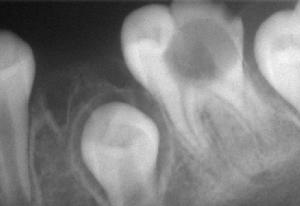

牙齒鄰面或頸區的齲蝕有時忽略,但只要仔細檢查即可發現,也可藉助X線檢查,牙片上齲洞部呈黑色陰影。

齲壞在X線片上呈黑色透射區,對難以確診者(如鄰面齲),可藉助X線片協助診斷。

若確定齲壞部位有困難,可拍攝X線牙片,齲壞處可見黑色陰影。有條件者可用光纖維透照、電阻抗、超音波、彈性模具分離、染色等技術,以提高齲病早期診斷的準確性和靈敏性。鑑別診斷